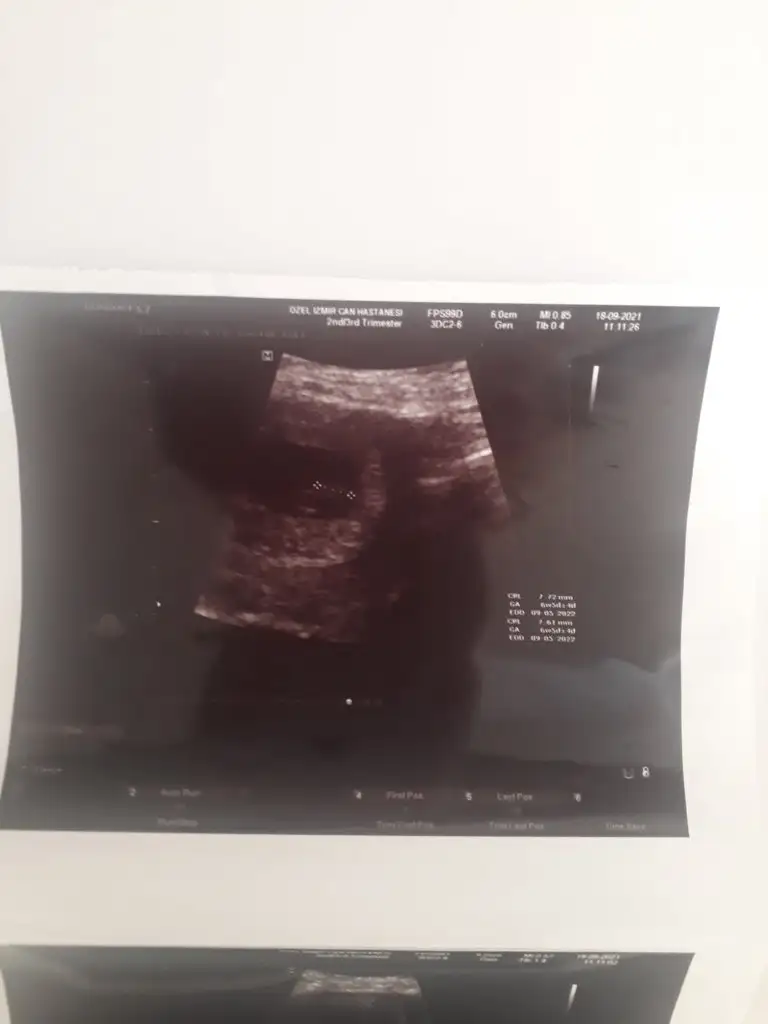

Ekliyim canim ben burda 6+2 ydi ama 6+5 gözükmüştü çok net değil görüntü ama niye evham yaptinkiKızlar 6+3 6+4 vb de kontrole gidip ultrason görüntüsü alanlar benimle paylaşabilir mi? Neden bilmiyorum ama evham yaptım biraz![]()